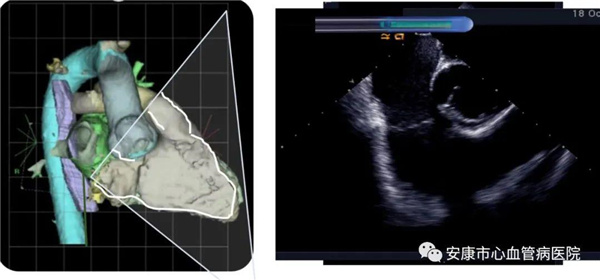

心律失常團(tuán)隊(duì)在11月6日為患者在ICE引導(dǎo)下行房撲射頻消融術(shù)。穿刺左鎖骨下靜脈,導(dǎo)絲走行證實(shí)了合并永存左上腔靜脈。穿刺右股靜脈,分別送入心腔內(nèi)超聲導(dǎo)管和消融電極,超聲下建立右心室、右心房、左心室、左心房、二尖瓣和三尖瓣及三尖瓣峽部模型。ICE就像術(shù)者多了一雙天眼,可以對(duì)心臟內(nèi)部結(jié)構(gòu)一目了然,360度無(wú)死角觀察心臟結(jié)構(gòu),可以做到“所視即所及”。建模后,消融三尖部峽部,房撲很快終止,轉(zhuǎn)為竇性心律,手術(shù)獲得成功!手術(shù)用時(shí)僅70分鐘,術(shù)后病情穩(wěn)定,安全返回病房。

心腔內(nèi)超聲(Intracardiac Echocaiography ICE)是將微型的換能器安裝在心導(dǎo)管的尖端,再經(jīng)外周血管(動(dòng)脈或靜脈)送至心腔,換能器發(fā)射聲波,然后將接受到的回波經(jīng)計(jì)算機(jī)處理后形成超聲圖像。由于換能器放置在心腔內(nèi),不受空氣等因素的干擾,因此比經(jīng)食道超聲檢查圖像更加清晰,可以辨別心內(nèi)的細(xì)微結(jié)構(gòu),臨床上主要用于指導(dǎo)心律失常的射頻消融治療。